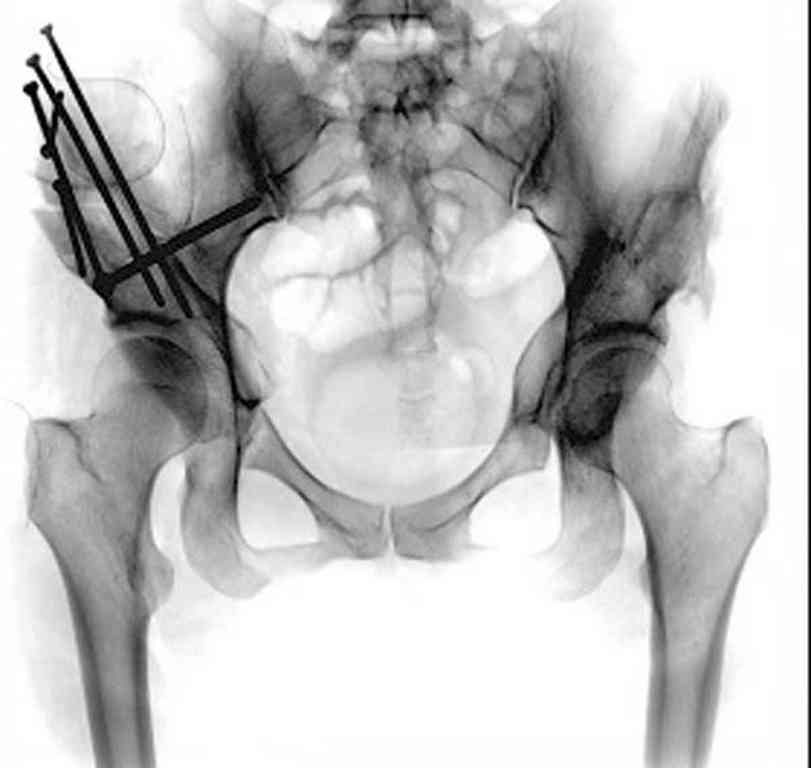

При более сохранном суставе от дальнейшего разрушения можно было бы сохранить только периориентацией нагрузки на сустав - Периацетабулярной Остеотомией .

После участия в последней конференции "Вреденовские Чтения" в Ст. Петербурге, по представленным докладам, я убедился, что в территории СНГ очень мало специалистов энтузиастов, кто серьезно занимается патологией дисплазии. В большинстве те, кто занимается данной патологией, делают давно забытую тройную остеотомию таза, и доложенные результаты находятся далеко от идеала...

Только коллеги из Вреденовского Института начали работу по тематике сохранения тазобедренного сустава, остеотомия как альтернатива замене сустава. Надеюсь, что скоро в России многие последуют примеру Ст. Петербурга, и тогда уменьшатся цифры по протезированию у молодых.